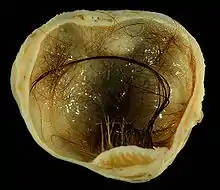

A small (4 cm) dermoid cyst of an ovary, discovered during a C-section | |

A dermoid cyst is a teratoma of a cystic nature that contains an array of developmentally mature, solid tissues. It frequently consists of skin, hair follicles, and sweat glands, while other commonly found components include clumps of long hair, pockets of sebum, blood, fat, bone, nail, teeth, eyes, cartilage, and thyroid tissue.